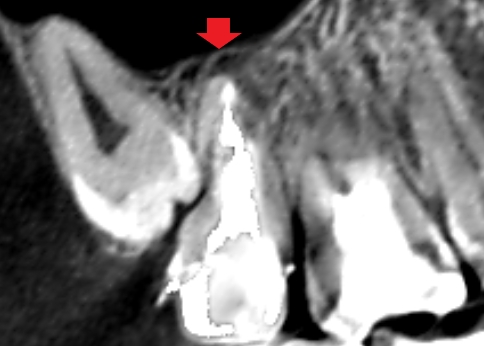

上顎第二大臼歯の矢状断のCT画像です。

赤い矢印の先に膿の影がみられます。